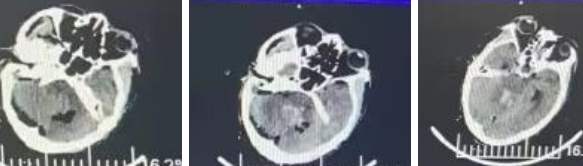

与家属沟通后,家属本着对医院的信任和救治亲人的迫切愿望,选择了脑室外引流+四脑室血肿清除术。手术由重医附二院黄宁医生,邻水县人民医院张俊波医生和叶海龙医生共同完成。术中首先进行右侧侧脑室前角穿刺,释放脑脊液,缓解脑积水和颅内高压。之后采取侧俯卧位后正中入路,去除部分后颅窝颅骨和寰椎后弓,显微镜下经膜帆入路清除血肿。膜帆入路是利用小脑和脑干之间的小脑延髓裂到达四脑室,这是脑组织的一个天然间隙,因此对小脑和脑干损伤小。此外膜帆入路暴露范围广,上方可到达中脑导水管出口,两侧可到达外侧孔。吸出血肿后清晰可见正中孔、闩、迷走神经三角等重要解剖结构(图2)。

图2

术后复查头部CT示大部分血肿清除干净(图3),患者于两天后苏醒,目前正在进行自主呼吸训练。 该手术是邻水县人民医院第一例经膜帆入路四脑室血肿清除术,患者家属的信任和科室团队技术力量成为了手术成功的关键。

图3